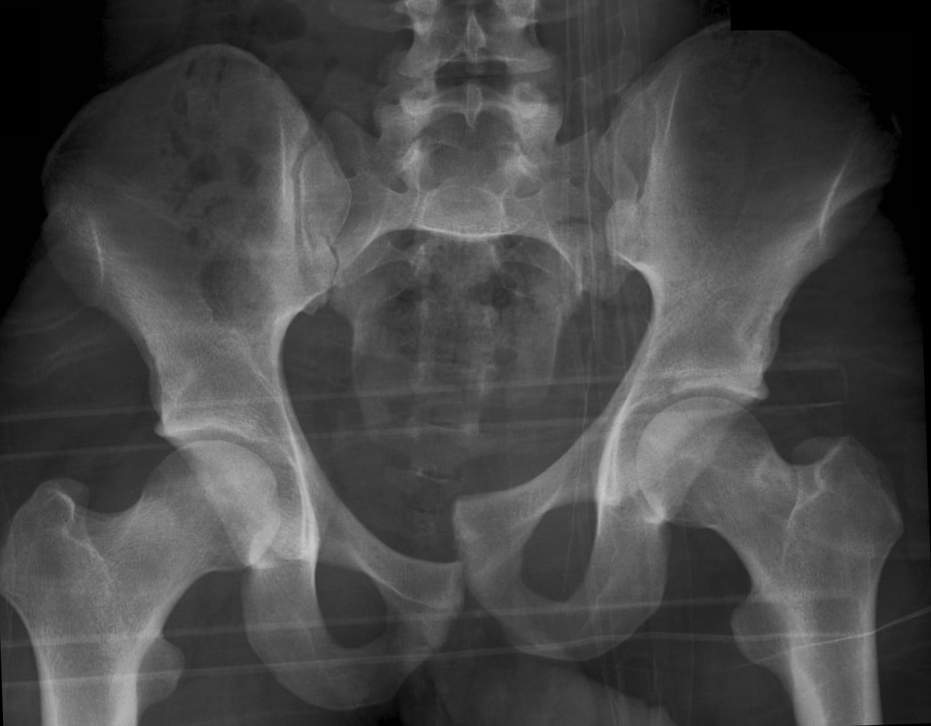

What is the most accurate description of this pelvic x-ray?

a) Vertical shear fracture

b) Anterior-posterior compression fracture

c) ‘Open book’ pelvic fracture

d) Normal pelvis

e) Lateral compression fracture

A